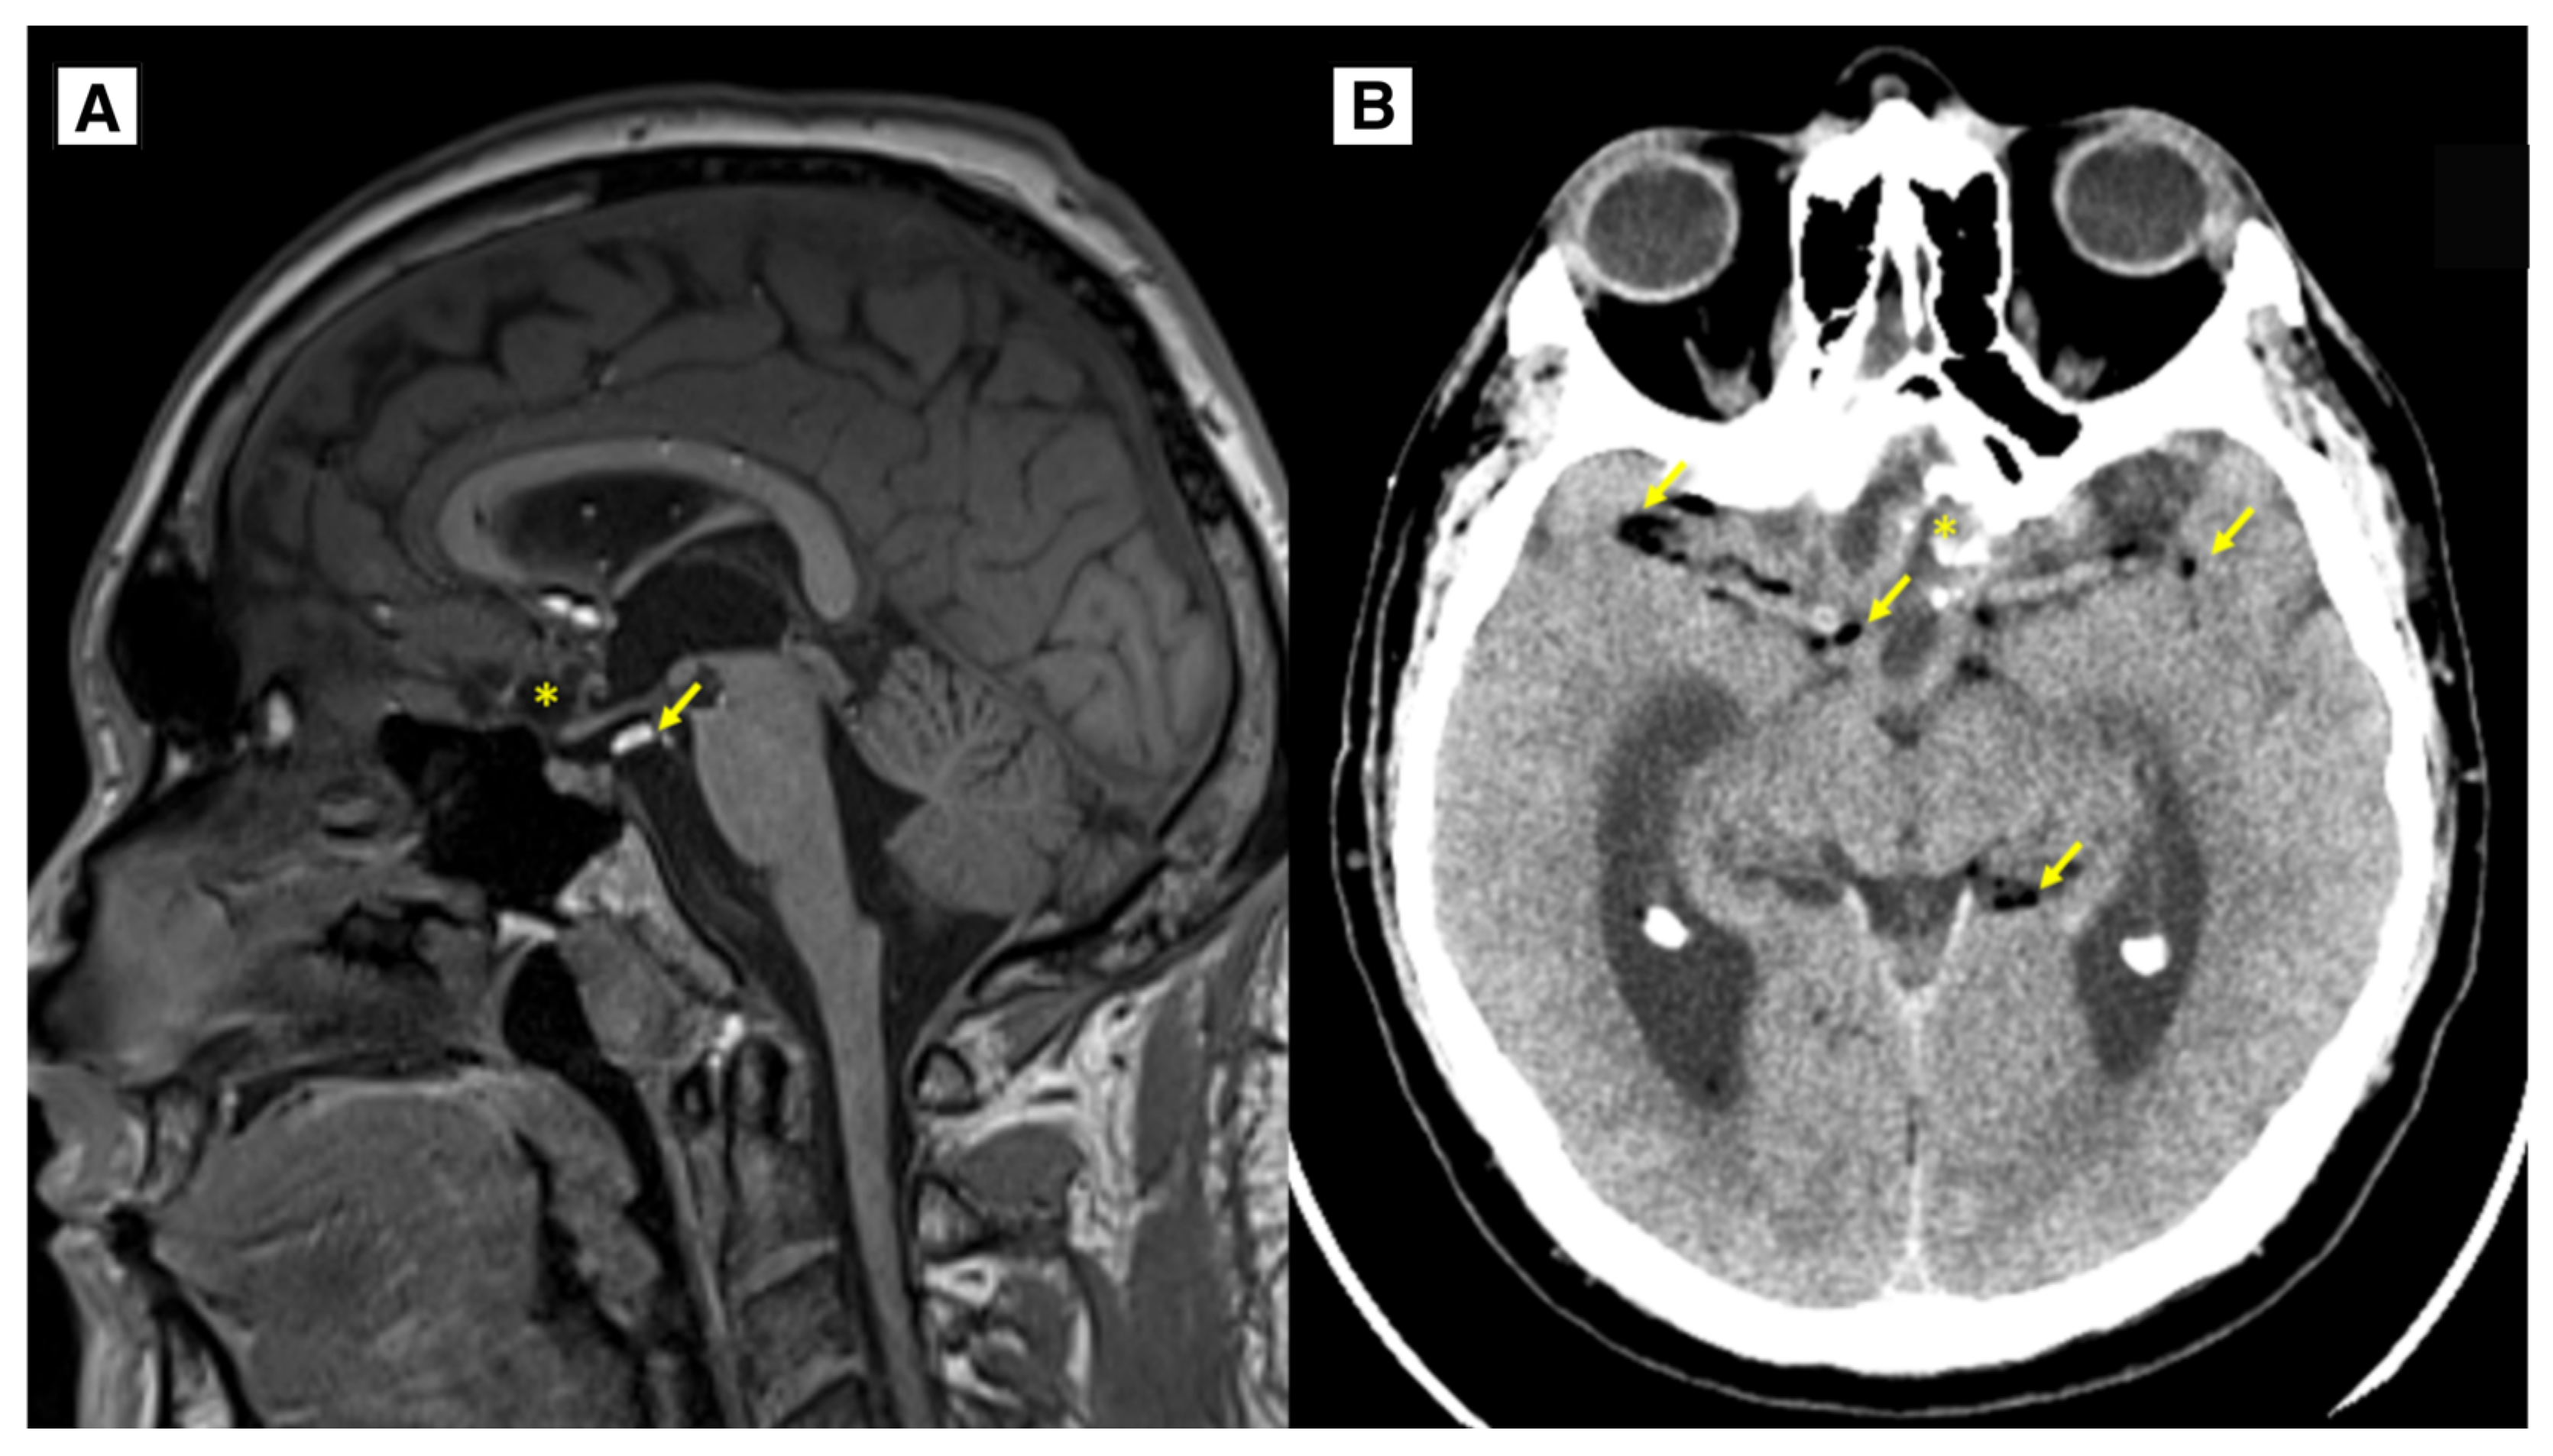

Figure 5.

Follow up. A: MRI of the brain T1W sagittal 1-year follow-up showing the dermoid cyst has been subtotally resected (*), there are very small fat lesions (yellow arrows), as well as residual calcifications of the dermoid along the left side of the post-operative lobe, as in the previous MR examination, small scarring changes with encephalomalacia in the dorsal parts of the gyrus recti of both frontal lobes. No data on progressions of dermoid cyst. B: CT of the brain 2-year follow-up showing intracranial dermoid cyst has been largely resected (*), there are very small fat lesions (yellow arrows). No data on progression of dermoid cyst. * – intracranial dermoid cyst, Arrows – punctate fat-containing lesions.

The patient was discharged from the hospital without any complaints. The patient’s overall health status was satisfactory, neurologically GCS was 15 points, no focal neurological deficit was seen. The surgical wound healed primarily. No recurrence and dermoid progression was noted on follow-up MRI imaging at 4 months, one year, and 2 years. MRI follow-up, performed 1 year after surgery, showed residual tissue of the tumour without volume increase, residual calcifications were also seen along the suprasellar region on the left side. Many punctate fat-containing lesions both along the ventricle wall and subarachnoid, similar to the previous MR examination (

Figure 5). Scarring changes, with encephalomalacia more in the right frontal lobe in the basal medial parts, extending more at the level of the gyrus recti, with minimal blood products. The optic nerve was not scarred, and no abnormal tissue was found around the optic nerve following neurosurgical treatment. It is important to monitor for any signs of optic nerve atrophy during follow-up MRI (

Figure 5).

33]. Residual calcifications of the dermoid may be seen along the front and left side of the postoperative lobe on a follow-up MRI one year post-surgery (